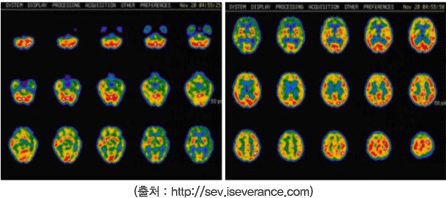

뇌 단일광자단층촬영(brain SPECT)

뇌혈류에 비례하여 분포하는 방사성의약품을 정맥주사하여 국소뇌혈류 및 신경수용체 영상을 얻어 뇌혈관 질환이 있거나 질환이 우려되는 환자의 진단, 뇌혈류 예비능을 평가하여 수술이 필요한지, 수술효과가 어떠한지, 질병의 경과가 어떠할지 예측할 수 있으며 간질 환자에서 간질병소를 찾아내어 수술 부위를 결정할 수 있습니다.뇌혈관 질환, 간질, 정신질환, 알쯔하이머병, 치매, 운동성 장애, 뇌종양 환자의 진단 및 여러 현상들의 병태생리학적 또는 기능적 기전에 대한 접근을 위하여 시행합니다.